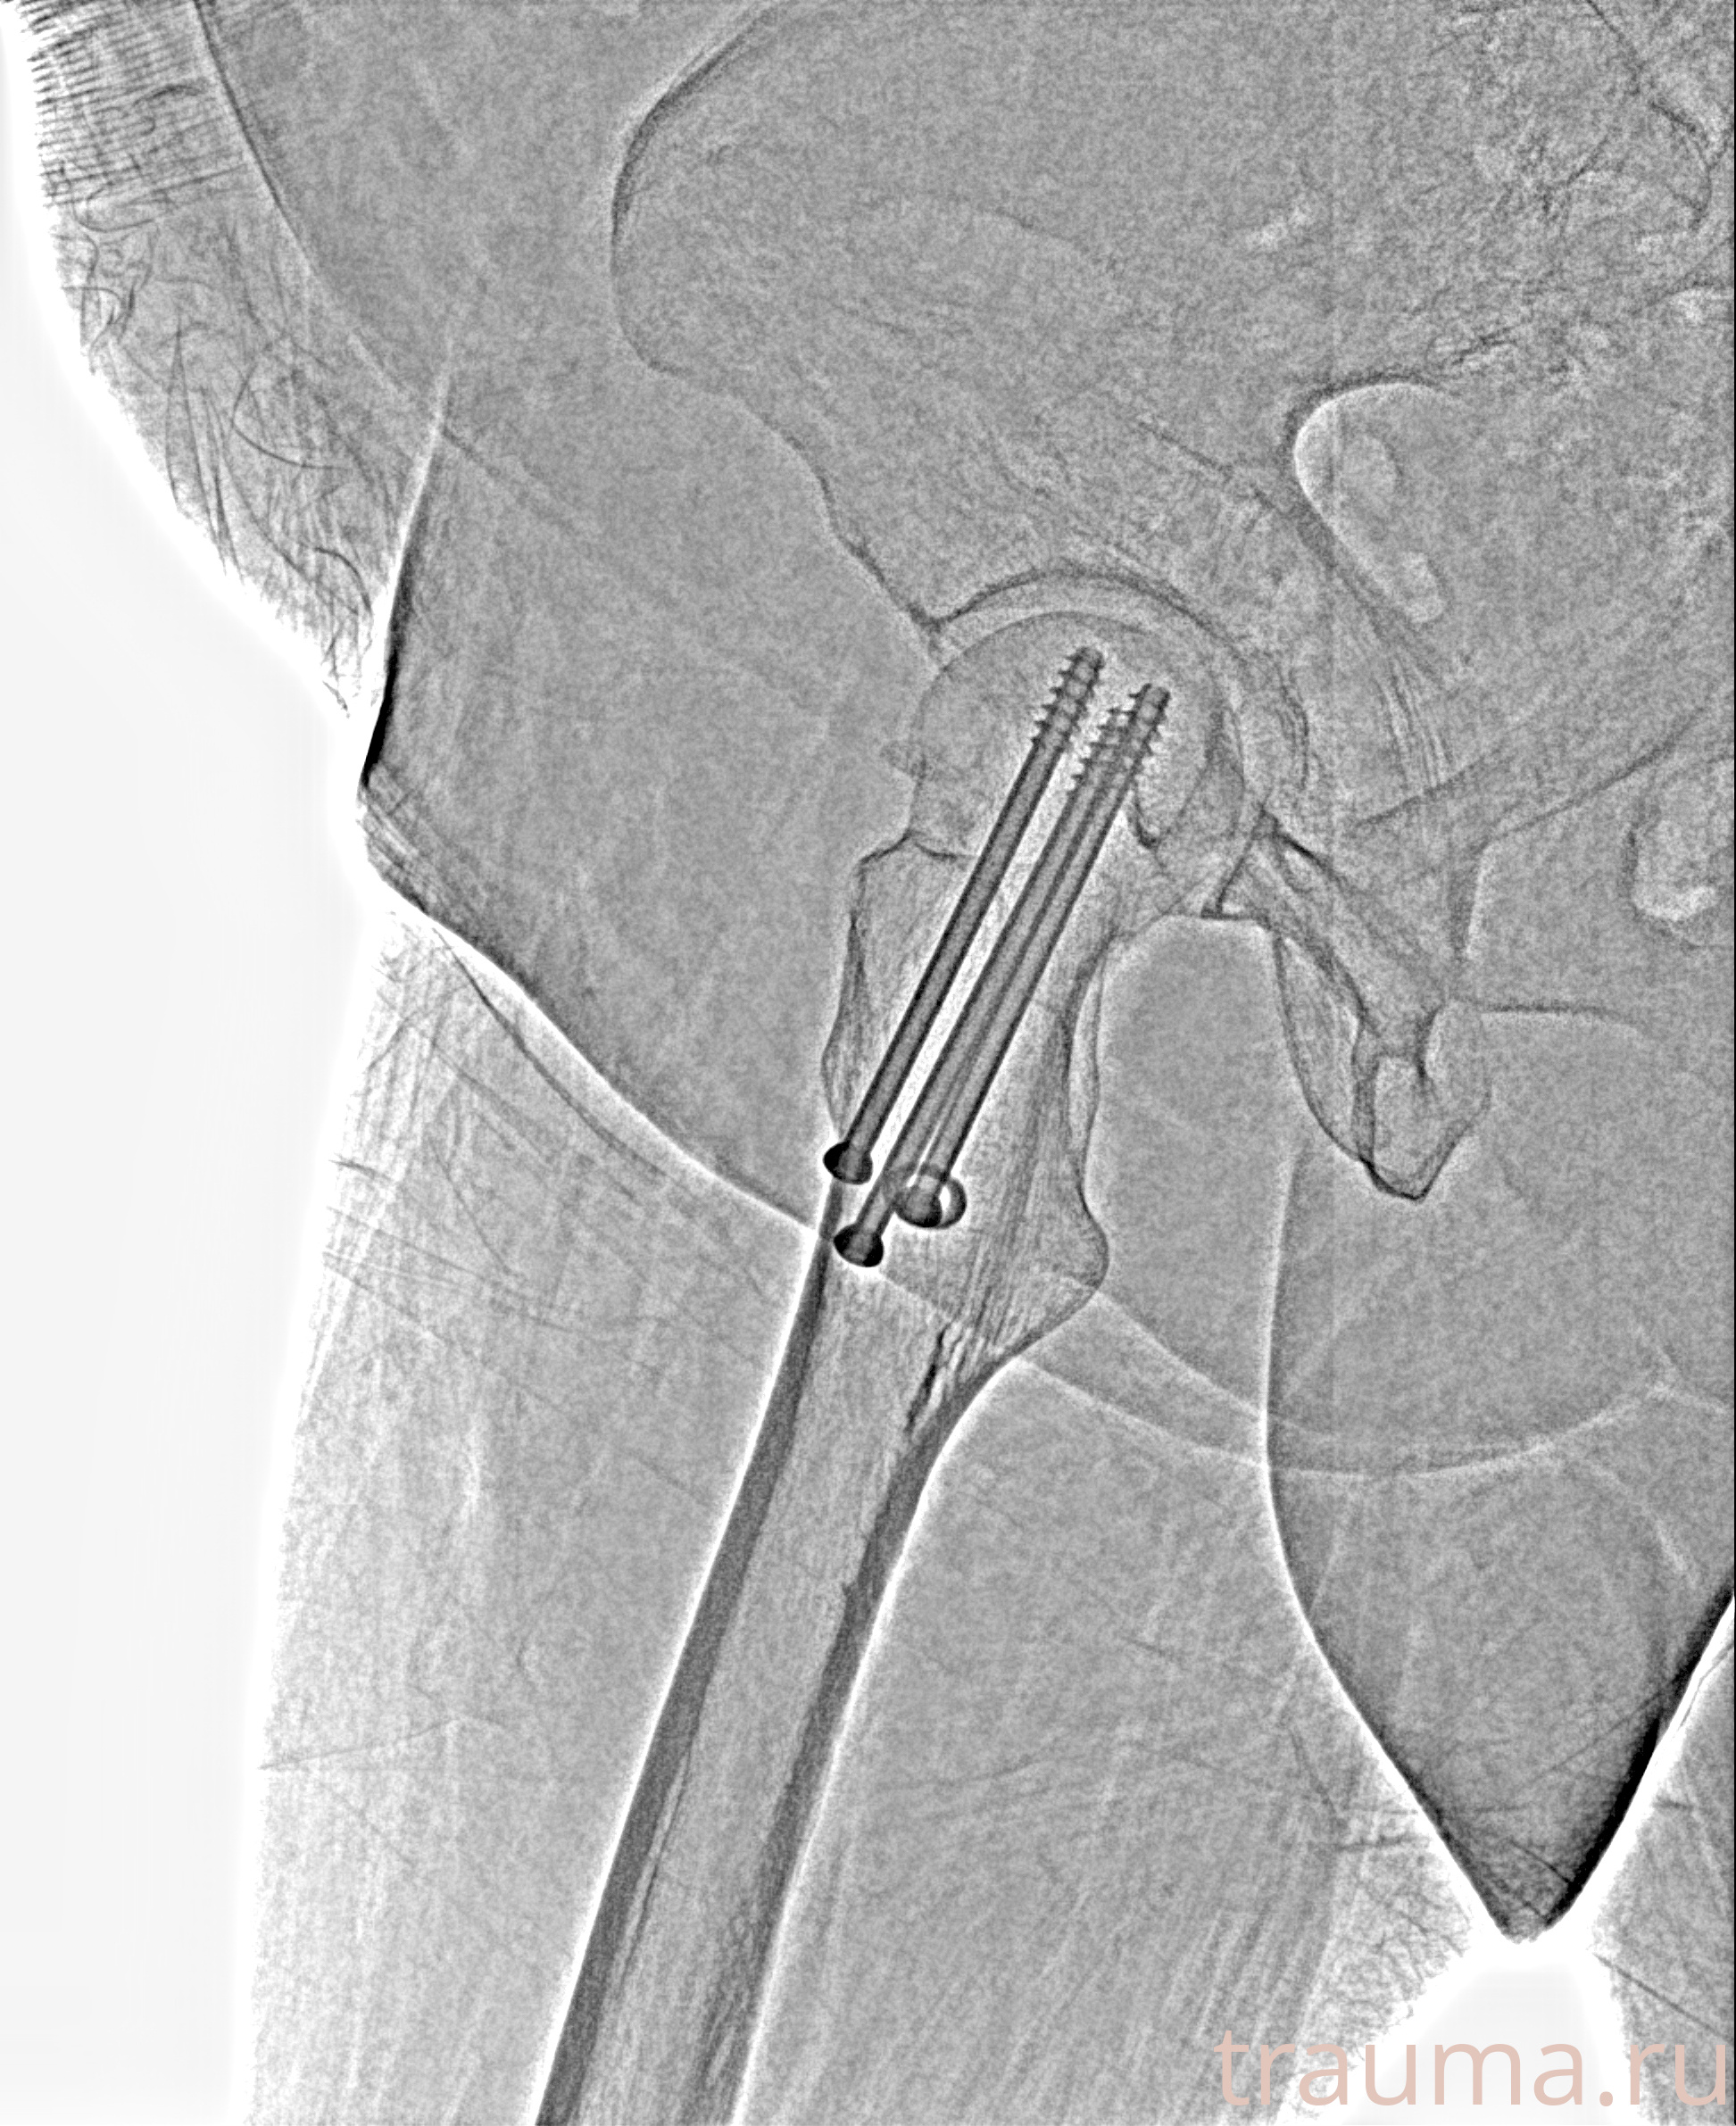

Рентгенограммы